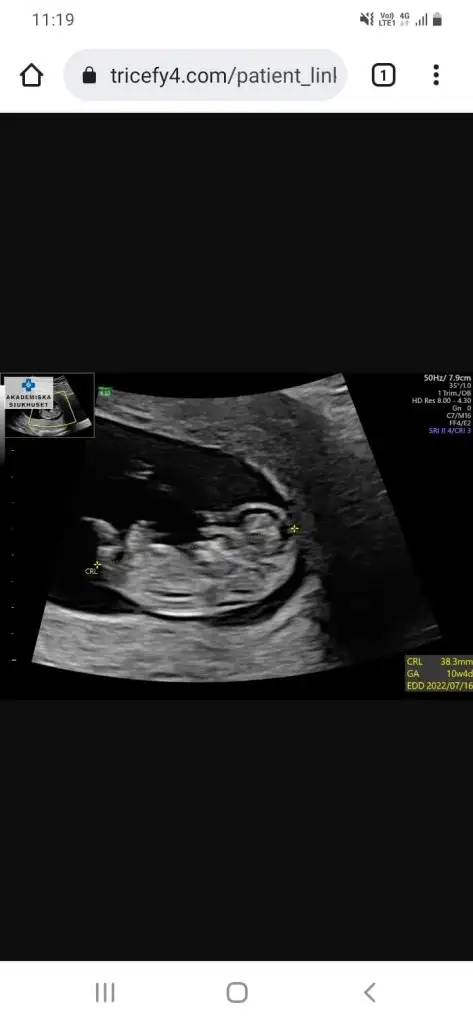

Selam kizlar 13-14 hafta sizce ne?